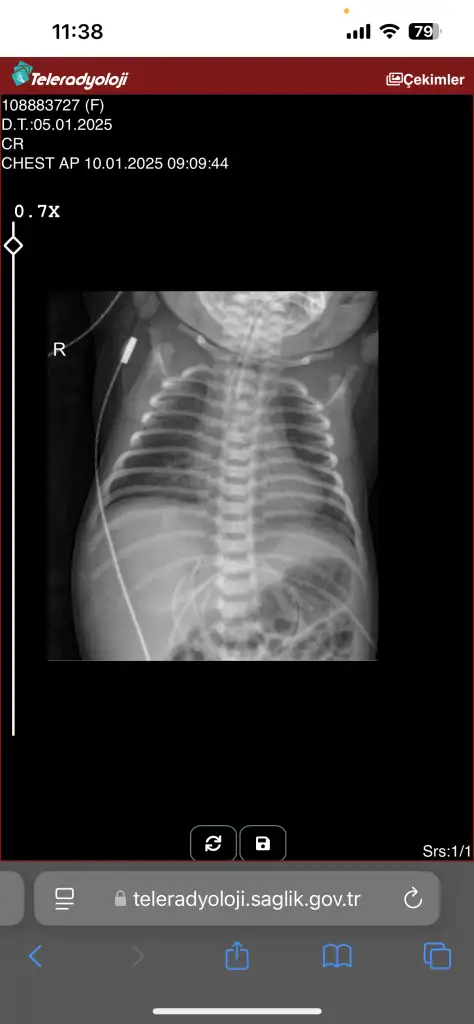

Veriyorlar yeni yeni. 2 gündür entübe değil ama bugün nasıl şuan bilemiyorum kan değerleri bu şekilde

Evet entübasyon hortumu görünmüyor iki hortum olmalıydı ağzında. Entübeden ayrılması da iyi bir şey süt de azıcık gaz yapmış hatta bebişe. Süt aldıkça bu değerler toparlanır. Kan gazına göre bebeğiniz solunumu tölere edebiliyor diyebiliriz bunlar güzel haberler